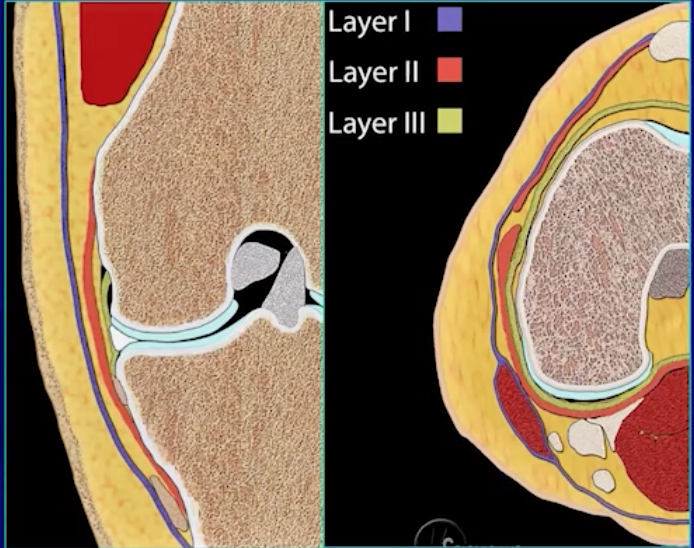

Medial Collateral Ligament (MCL)

• 3 Layers

• Superficial layer -

• fuses with medial retinaculum of patella

• Middle layer -

• aka tibial-collateral ligament

• fuses with MPFL

• Deep layer (2 parts)

• Menisco-capsular attachment to femur

• Curves up from meniscus to attach on distal and lateral edge of femur

• Menisco-tibial ligament

• Curves down from meniscus to proximal and lateral edge of tibia

• Can be thought of in 2 ways, layers or thirds

• Layers

• Layer 1 = fascia

• Layer 2 = Superficial MCL

• Layer 3 = Deep MCL and capsule

• Issue here is that many of these will fuse

• Anteriorly layers 1 & 2 fuse to medial retinaculum

• Posteriorly 2 & 3 fuse to posterior oblique ligament